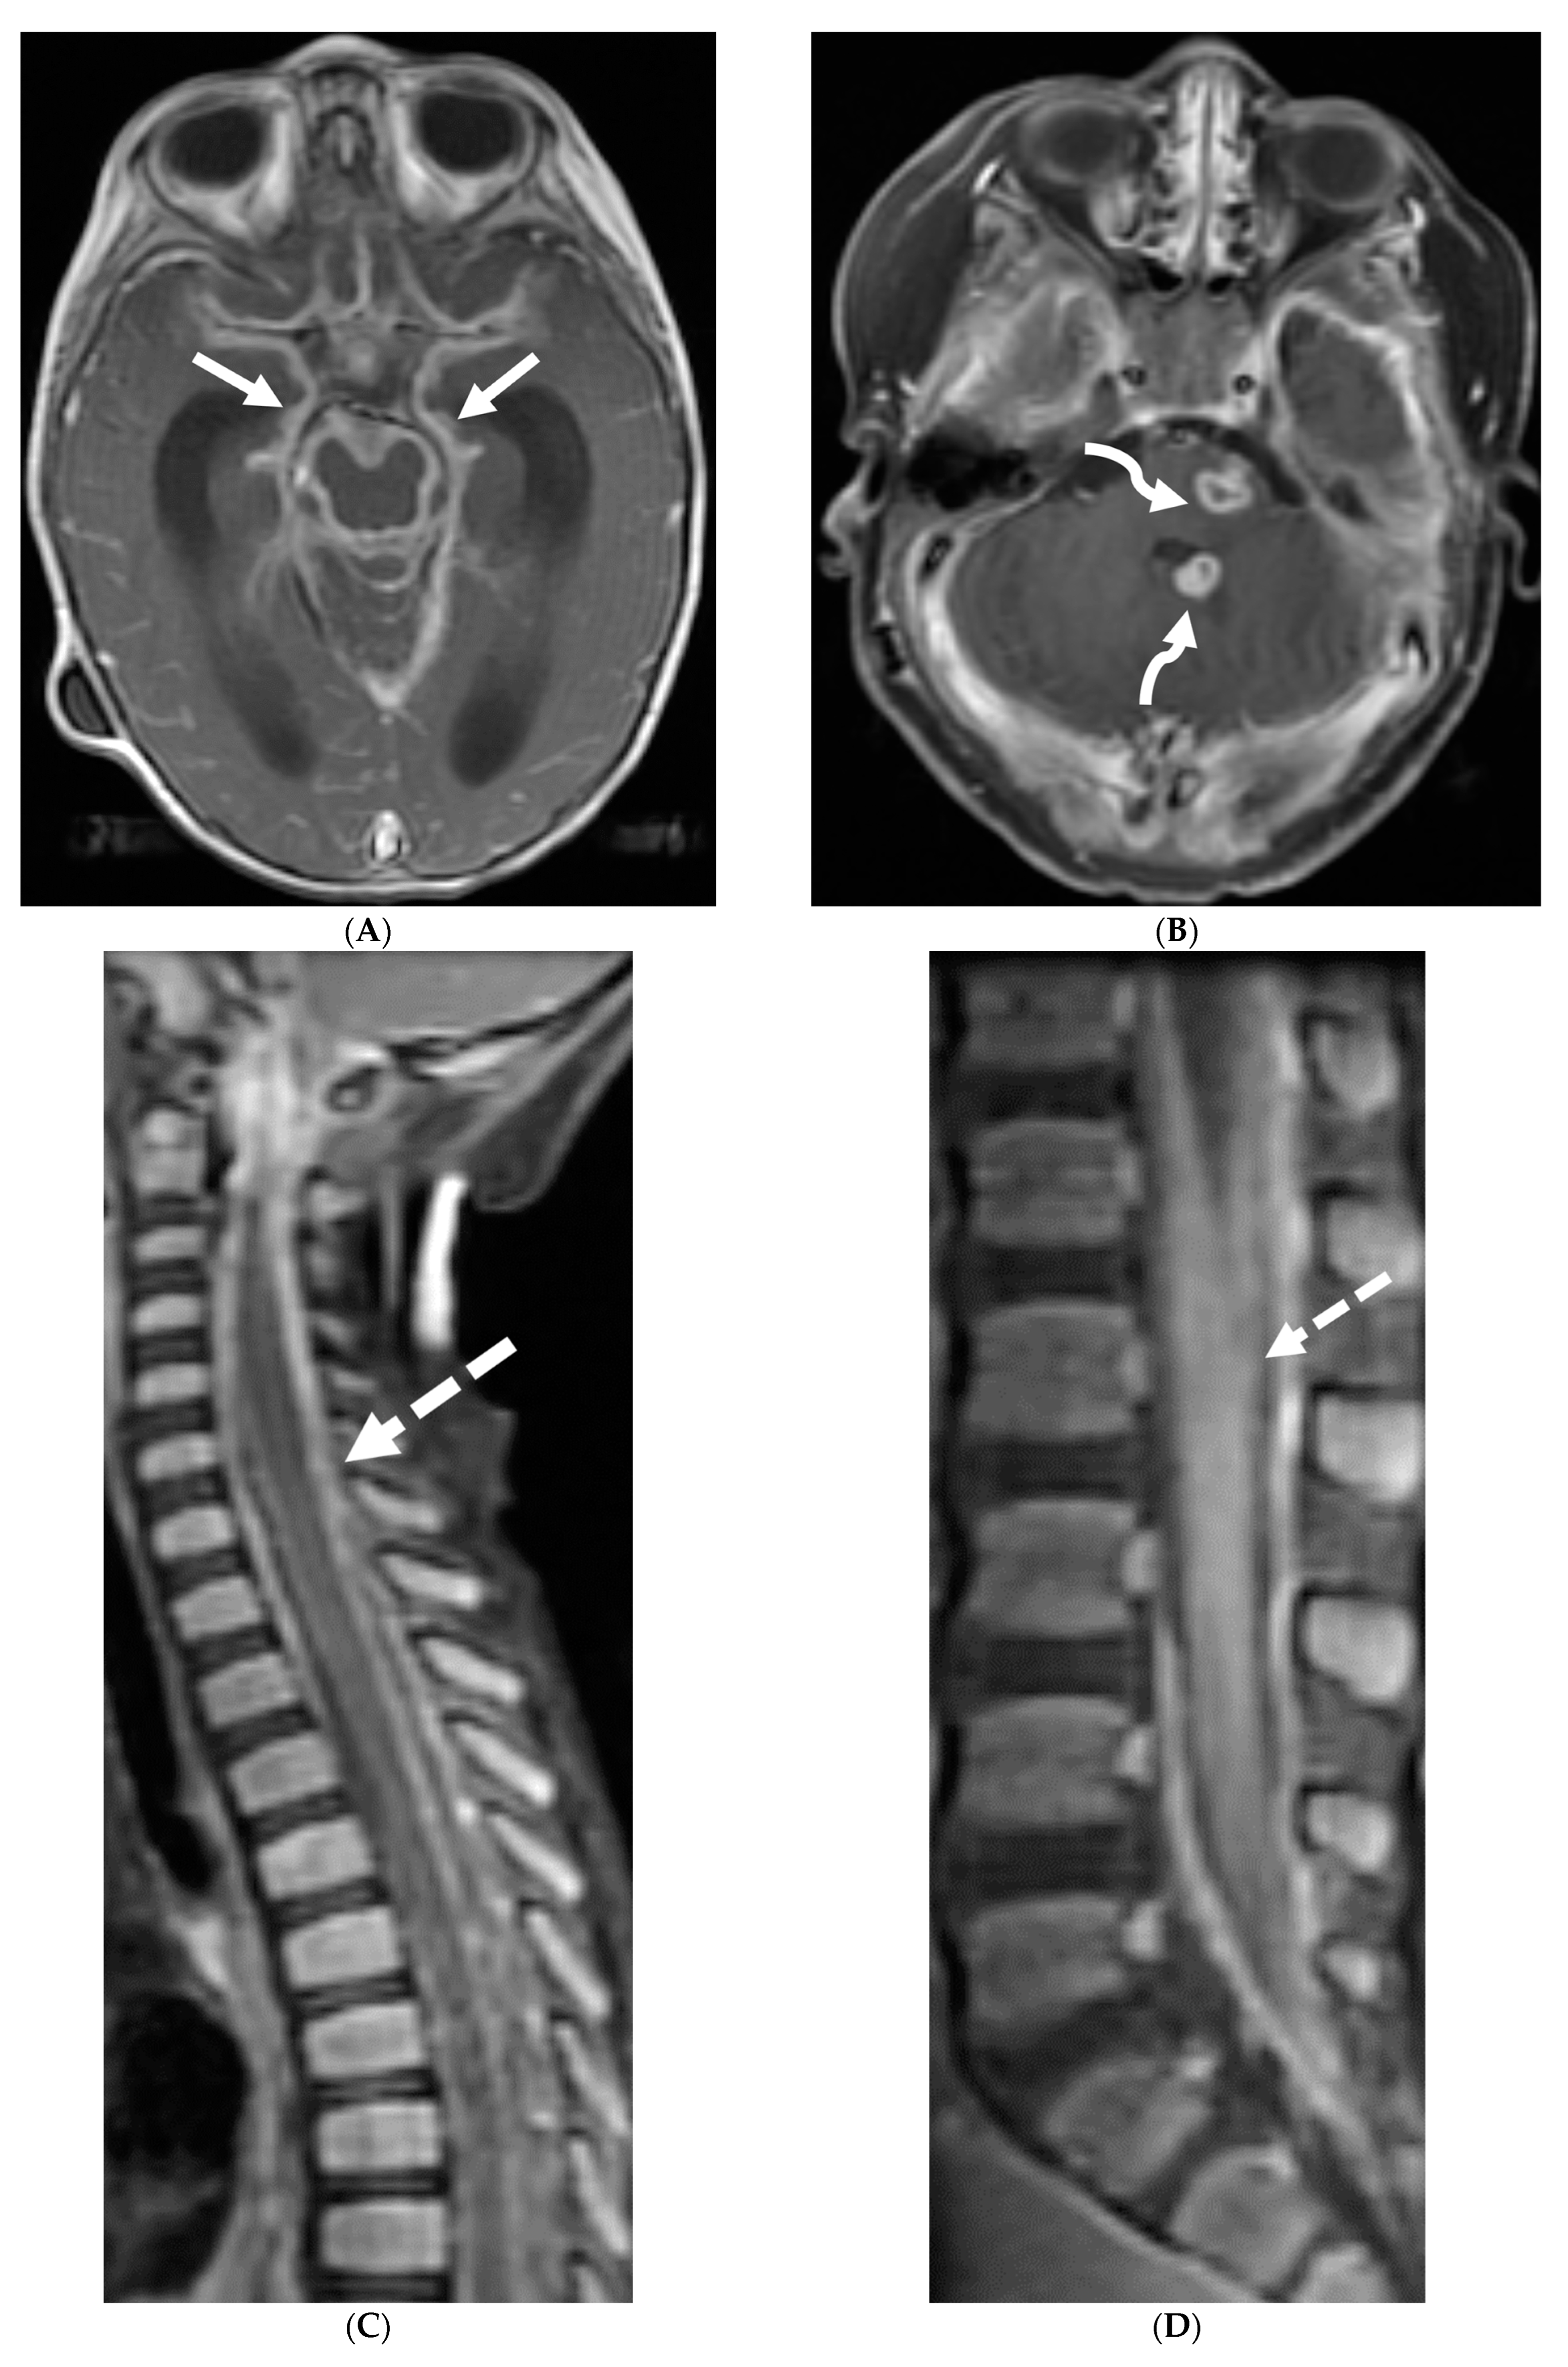

4.1. Bacterial Meningitis

Hematogenous dissemination is the primary cause of bacterial spread to the CNS. The most common infective organisms differ according to age with Group B Streptococcus and Escherichia coli commonly affecting neonates and Streptococcus pneumoniae, Neisseria meningitidis, Haemophilus influenzae (decreasing due to vaccination) occurring in infants and children. Post contrast T1 and FLAIR sequences are the primary ones to demonstrate LME [73]. However, multiple associated parenchymal abnormalities occur in childhood, particularly in neonates due to different causative organisms.

Group B streptococci causes ischemic infarcts along vascular territories in an asymmetric fashion in neonates. Non diffusion restricting extra-axial collections can also occur which tend to resolve on follow up imaging without any sequelae. An important imaging differential in this age group is of hypoxic ischemic encephalopathy (HIE), often with symmetric diffusion restriction in metabolically active regions [74].

E. coli is another common neonatal and infantile cause of bacterial meningitis. There is characteristic diffusion restriction in the extra-axial collections along with ventriculomegaly and/or ventriculitis [74]. To note, extra-axial empyema is also common with S. pneumoniae, but occur in an older age group. Serratia marcescens and Citrobacter are two uncommon pathogens causing meningitis in neonates with fulminant disease course. They lead to large parenchymal abscesses with striated appearance on T2W images and foci of susceptibility. N. meningitidies causes typical gyriform cortical enhancement consistent with cerebritis predominantly involving the occipital lobes (Figure 12) [74].

Figure 12.

Axial DWI (A), axial SWI (B), sagittal T2 (C), axial ASL (D) and coronal T1 post contrast (E): 11-day-old female presented with seizures and lethargic. Restricted diffusion is noted in the sulci along the bilateral frontal convexities, concerning for meningitis (arrows). Curvilinear susceptibility in the extra-axial spaces of bilateral frontal convexities, consistent with thrombosed cortical veins (curved arrows). Cortical T2 hyperintensity is seen in the bilateral frontal and parietal lobes with corresponding hyperperfusion in keeping with extensive cerebritis (dashed arrows). Diffuse leptomeningeal and pachymeningeal enhancement is seen (open arrows). Overall features represent meningitis and cerebritis. Cerebrospinal fluid analysis: Group B streptococcus.

4.2. Tuberculosis

Tuberculous meningitis (TBM) is a severe form of extrapulmonary tuberculosis, associated with high morbidity and mortality rates in those under 5 years old. Case fatality rate reaches up to 20% and only one-third of the patients having no long term neurological sequelae [75]. In developed countries, while the overall incidence of tuberculosis has declined, TBM remains a concern in pediatric populations, particularly among high-risk groups such as immunocompromised children and those from TB-endemic regions. Clinical presentation in children can be subtle and nonspecific, especially in younger age groups. Initial symptoms may include low-grade fever, irritability, poor feeding, and vomiting, which can progress to more severe manifestations such as altered mental status, focal neurological deficits, and seizures.

TBM is characterized by LME, predominantly smooth and localized in the basal cisterns [76]. In severe cases, this can lead to the formation of basal exudates, visible as enhancing fluid in the basal cisterns [77]. The disease is often accompanied by parenchymal abnormalities, most commonly conglomerated ring-enhancing lesions with characteristic T2 hypointensity due to caseous content, although liquefaction may cause the core to become T2 hyperintense [78]. These ring-enhancing lesions can potentially coalesce to form abscesses. TBM may also present with infarcts in the thalami or basal ganglia due to basal vasculitis (Figure 13) [78]. The meningeal involvement typically occurs through hematogenous spread, and the condition is most prevalent in children and young adults presenting with altered mental status [79]. These imaging findings along with lymphocyte predominant CSF and significantly high protein can be diagnosed as tuberculosis since culture can take weeks.

Figure 13.

Axial T1 FS (A,B) and sagittal T1 fat sat (C,D). 2-year-old girl presented with emesis, fever and status epilepticus. Septic work up revealed tubercular meningitis. Extensive abnormal enhancement is seen in the meninges, prominent in the basilar cisterns (arrows). Ring-enhancing tuberculomas are seen in the cerebellum adjacent to the fourth ventricle and in the brainstem (curved arrows). Diffuse meningeal enhancement and thickening throughout the spinal canal as well as enhancement of the nerve roots is seen (dashed arrows).